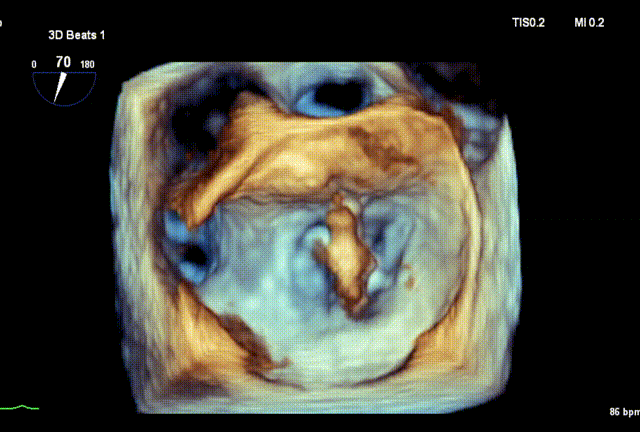

术前3D

DMR P2脱垂连枷(脱垂范围:12mm,连枷间距:3mm),反流2区,MR重度(VC:4* 10mm),A2:21mm,P2:10mm,AP:30mm,MVA约 4.7 cm²。